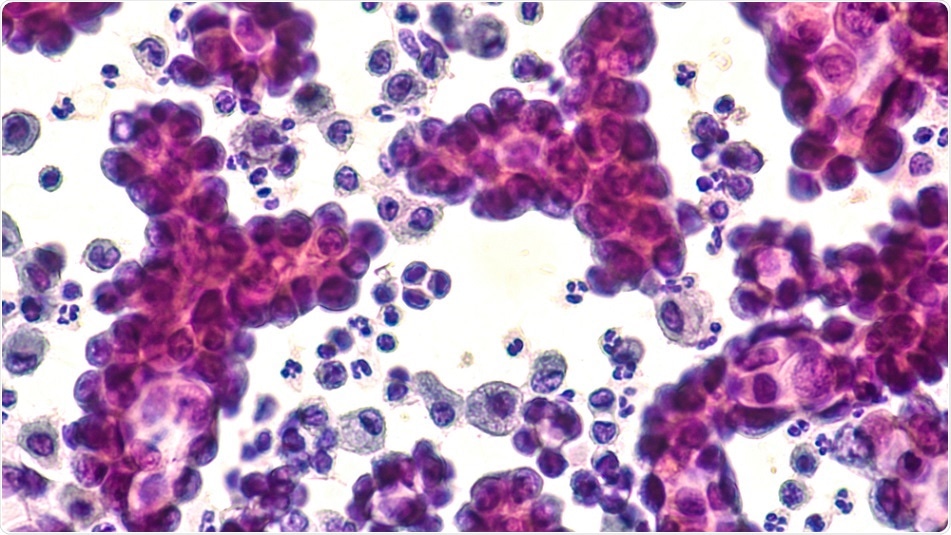

Shutterstock | David Litman